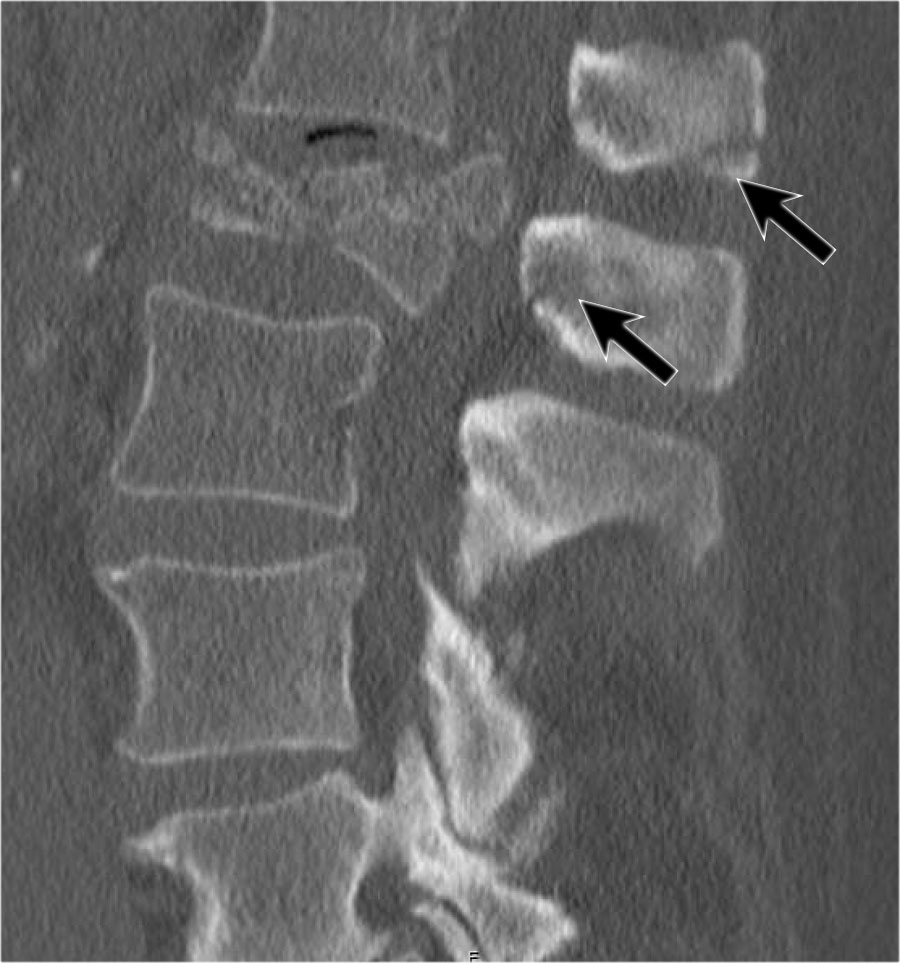

Mảnh xương góc sau trên thân đốt sống bị đẩy lùi ra sau (Retropulsion)

Hiện tượng mảnh xương bị đẩy lùi ra sau là đặc điểm điển hình của gãy vỡ, phân biệt rõ ràng với gãy nén đơn thuần.

Cuộn qua các hình ảnh.

Gãy theo mặt phẳng đứng dọc của thân đốt sống và

cung sau đốt sống

Gãy theo mặt phẳng đứng dọc của thân đốt sống và gãy cung sau theo mặt phẳng đứng dọc gặp lần lượt trong 90% và 85% các trường hợp gãy vỡ.

Dưới đây là bốn ví dụ minh họa.

Trong phân loại Denis, đây sẽ là gãy ba cột — trước/giữa/sau — cho thấy gãy xương rất không vững.

Tuy nhiên, trong phân loại TLICS, đây là gãy vỡ, tức là 2 điểm cho hình thái.

Phương pháp điều trị sẽ phụ thuộc vào tính toàn vẹn của PLC và tình trạng thần kinh.

Giãn rộng khoảng cách liên cuống (interpedicular distance)

Giãn rộng khoảng cách liên cuống, thường là hệ quả của đường gãy theo mặt phẳng đứng dọc, gặp trong 80% các trường hợp gãy vỡ.

Hình chiếu bên cho thấy các đặc điểm điển hình của gãy vỡ.